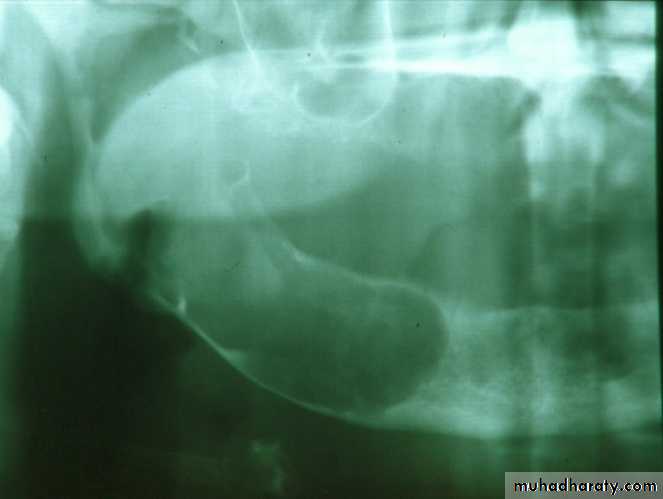

d. Tuberosity reductionPreprosthetic Surgery

d. Tuberosity reduction

Preprosthetic Surgery